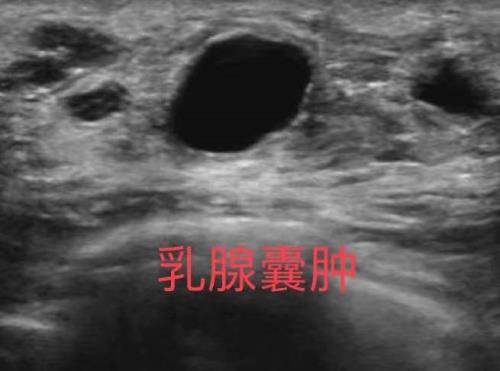

乳腺彩超检查是利用超声仪器将超声波发射到乳腺获得声像图,根据声像图显示的病灶的大小、形态、轮廓边界、回声类型、回声内部情况及后方衰减情况等判断病变的性质。

在乳腺自我检査或体检触摸到乳腺肿块时。2、发现乳头有溢液,尤其是血性时或乳头内陷以及局部皮肤的改变。3、无症状的乳腺癌的高危人群,可以定期做乳腺的超声检查。4、发现乳腺肿块时,鉴別肿块的性质,如肿块是囊性,囊实性或者是良恶性的鉴别。5、乳腺出现炎性表现时,用于鉴别急性乳腺炎、乳腺脓肿和炎性乳腺癌。6、乳腺良性病变的随访以及乳腺癌术后的随访。7、美容隆胸后及其并发症的监测。 8、具有乳腺高危人群,包括:初潮年龄早、绝经年龄晚、晚婚、晚育、未生育、未哺乳、乳腺癌家族性遗传史、有烟酒嗜好的女性等。

1、乳腺彩超检查操作简便、安全、无辐射,并可多切面、动态观察及测量肿块血流,对受检者无痛苦,无放射性损害,可以短期多次反复进行,适用于任何年龄层女性,包括妊娠期和哺乳期女性。2、乳腺彩超检査能较好的显示乳腺肿块的特征,可鉴别在X线片上看不到,但可触及的肿物,也可用于不能行乳腺钼靶检査的女性(如孕妇等)。3、超声对软组织有良好的分辨力,能够清晰的显示乳房及胸壁的各层结构,可以确定病变的解剖部位和层次,鉴别乳腺肿块和胸壁肿块。4、根据声像图表现,结合血流,可以推断肿块的良恶性,并可发现有无局部及远处转移。5、若发现乳房有肿块,还可在超声引导下进行穿刺、活检及治疗。6、随访方便。